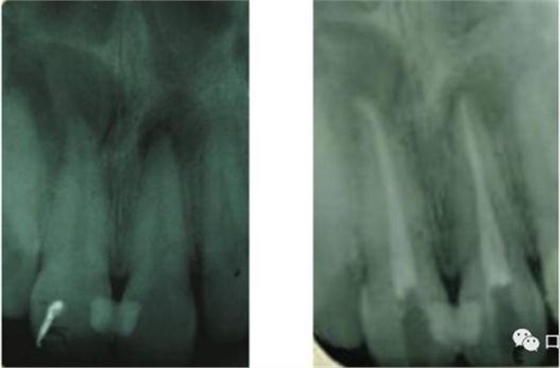

41 治療前X光片

激光治療中

6個(gè)月后治療效果

46治療前X光片

半導(dǎo)體激光治療中